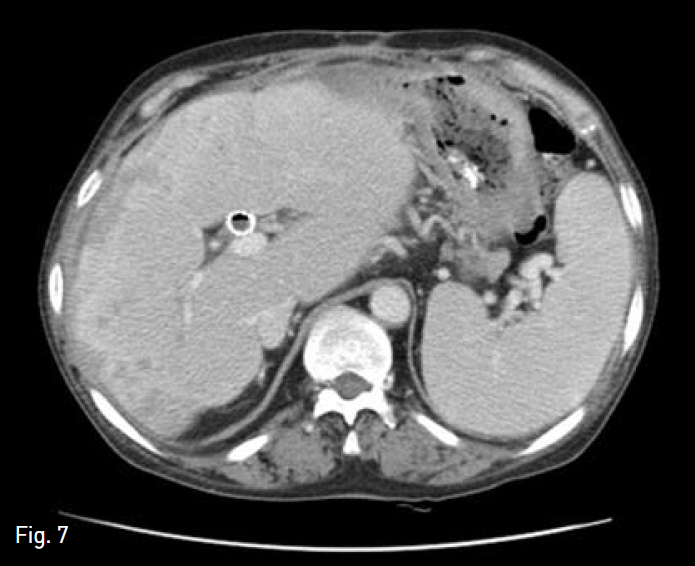

Fig. 7

Follow-up axial abdominal CT image, obtained 5 months after stenting, shows size reduction of right hepatic lobe with minimal abscess pockets and com pensatory hypertrophy of caudate lobe.